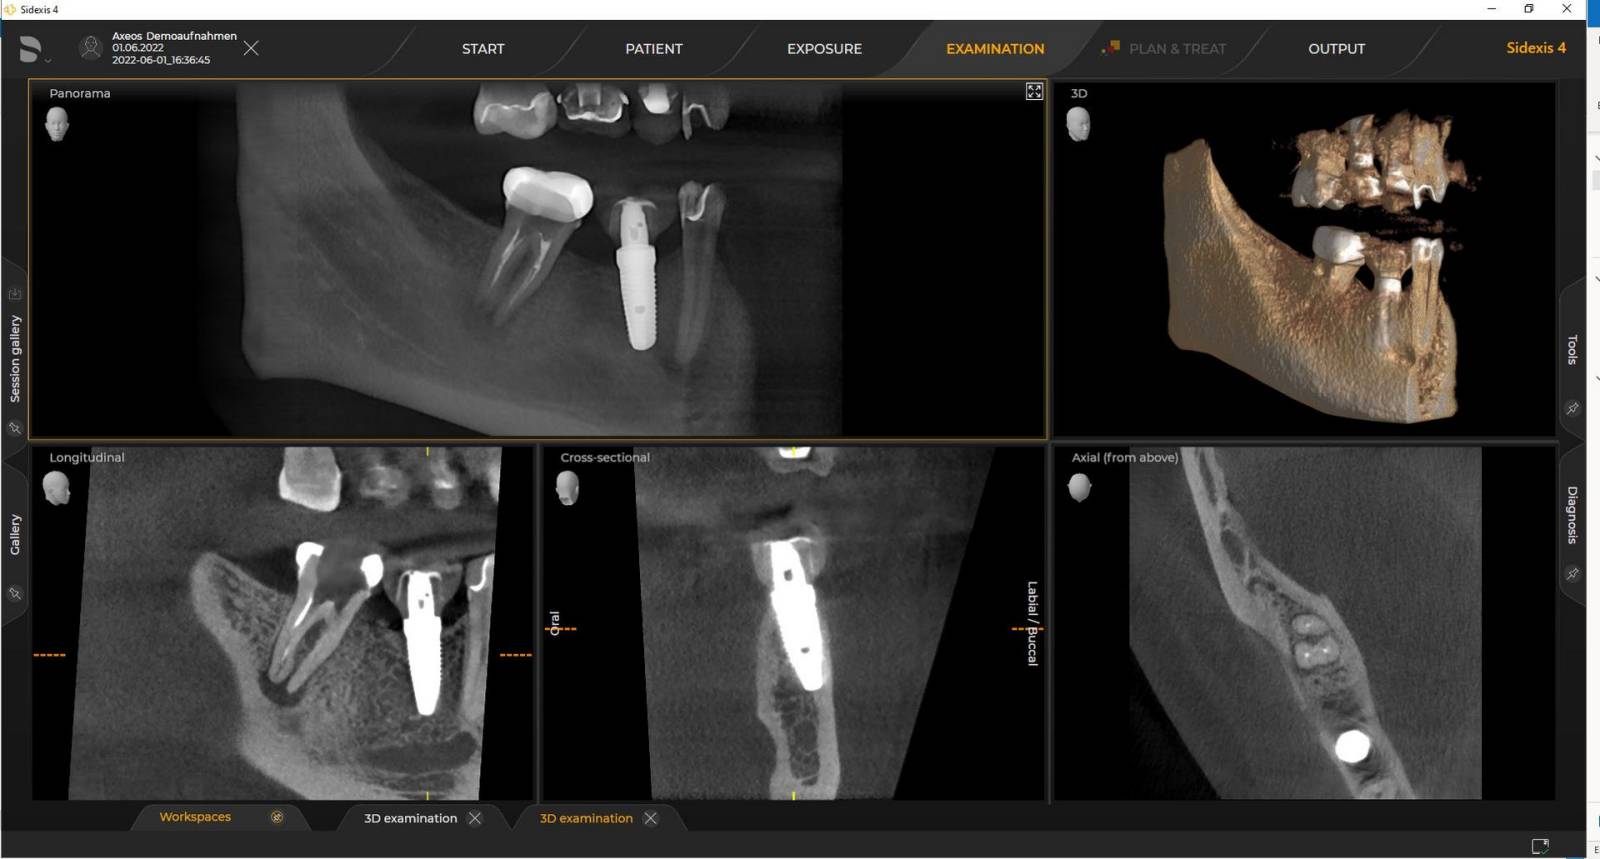

Numerous volume sizes ensure flexibility in everyday practice. Examine a precise area or evaluate the complete dentition including the TMJs

With the Intelligent Low Dose mode, you get 3D images in the dose range of a 2D X-ray. In HD mode (up to 1,400) individual images are captured during a single rotation and converted into a 3D volume with up to 80 μm for low-noise images in high resolution

Dentsply Sirona 3D units work exclusively with Sidexis 4. Nevertheless data migration from Sidexis XG to Sidexis 4 is very easy. Sidexis 4 allows for the full digital experience with the latest tools.